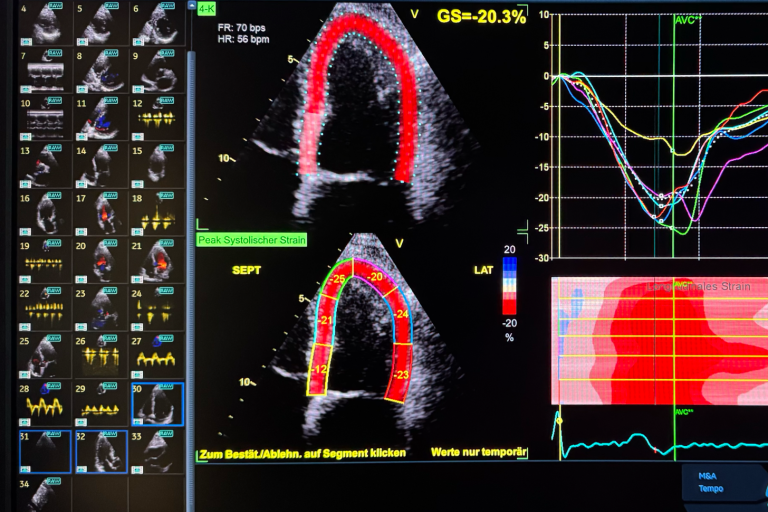

Echokardiographie

Die Echokardiographie, auch Herzultraschall genannt, ist ein bildgebendes Verfahren, das eine detaillierte Beurteilung von Herzstruktur und Herzfunktion ermöglicht. Mithilfe moderner Ultraschalltechnik können Bewegungen der Herzwände und Klappen in Echtzeit dargestellt werden. Dabei lassen sich die Pumpfunktion des Herzens genau bestimmen, die Herzklappenfunktion zuverlässig beurteilen und Herzmuskelerkrankungen bereits in einem frühen Stadium erkennen. Die Untersuchung verläuft völlig schmerzfrei und ohne Strahlenbelastung. Sie liefert wertvolle Informationen für die Einschätzung der allgemeinen Herzgesundheit, die Planung individueller Therapien und die Kontrolle bestehender Herz-Kreislauf-Erkrankungen. So trägt sie wesentlich zur Früherkennung und gezielten Behandlung von Herzerkrankungen bei.